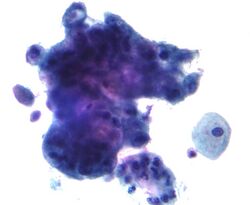

Cervical cancer ranks among the top three most common cancers among women in Latin America, sub-Saharan Africa, and parts of Asia. Cervical cytology screening aims to detect abnormal lesions in the cervix so that women can undergo treatment prior to the development of cancer. Given that high quality screening and follow-up care has been shown to reduce cervical cancer rates by up to 80%, most developed countries now encourage sexually active women to undergo a Pap test every 3–5 years. Finland and Iceland have developed effective organized programs with routine monitoring and have managed to significantly reduce cervical cancer mortality while using fewer resources than unorganized, opportunistic programs such as those in the United States or Canada.[68]

In developing nations in Latin America, such as Chile, Colombia, Costa Rica, and Cuba, both public and privately organized programs have offered women routine cytological screening since the 1970s. However, these efforts have not resulted in a significant change in cervical cancer incidence or mortality in these nations. This is likely due to low quality, inefficient testing. However, Puerto Rico, which has offered early screening since the 1960s, has witnessed almost a 50% decline in cervical cancer incidence and almost a four-fold decrease in mortality between 1950 and 1990. Brazil, Peru, India, and several high-risk nations in sub-Saharan Africa which lack organized screening programs, have a high incidence of cervical cancer.[68]